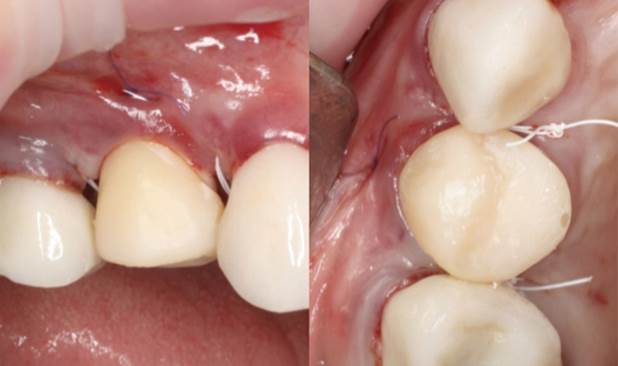

Clinical case: Extraction, immediate implant placement, & provisionalization

- Courtesy of Dr. Iulian Filipov, Romania -

Keywords

AnyRidge, R2GATE, guided surgery, immediate placement, immediate provisionalization, initial stability, Dr. Iulian Filipov, #25, maxillary posterior, immediate loading, Mega ISQ

Products:

AnyRidge implant system, R2GATE, MEGA ISQ, Digital prosthesis